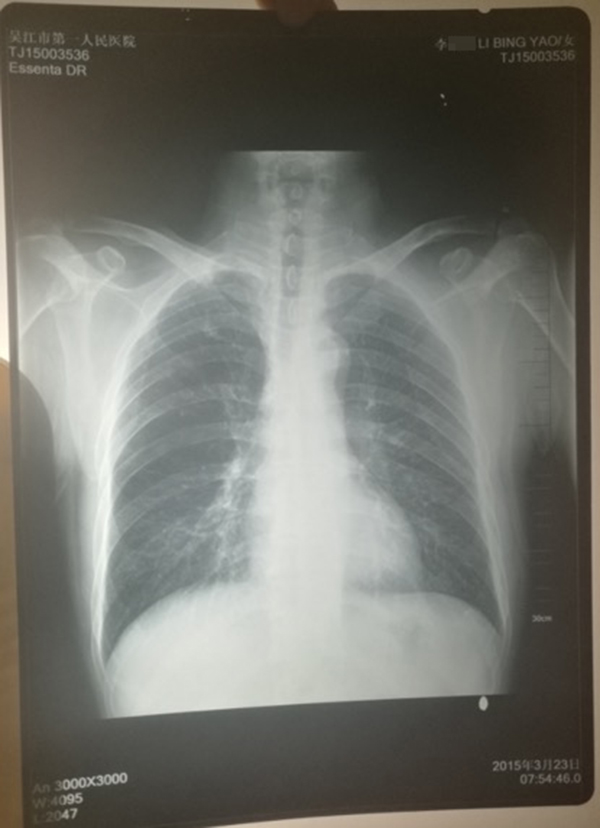

醫(yī)院提供的計(jì)建宏的“真實(shí)胸片”,寫有姓名“李某某”。 受訪人供圖

計(jì)云強(qiáng)稱,吳江區(qū)第一人民醫(yī)院曾提供一份印有“李某某”姓名的胸片,并稱該胸片才是計(jì)建宏的“真實(shí)影像結(jié)果”。

對(duì)于“李某某”姓名的胸片,上述吳姓主任稱,經(jīng)過(guò)醫(yī)院核查,兩份胸片的結(jié)果都是“正!钡模叭绻Y(jié)果是不一樣的話,那么問(wèn)題就大了,但是因?yàn)槭且粯拥慕Y(jié)果,所以不能認(rèn)為是‘漏診’或‘誤診’!